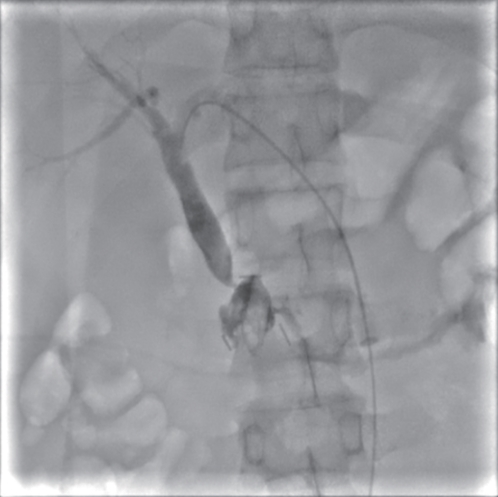

Successful treatment of biliary fistula after Beger surgery by oral choledochoscopy-assisted percutaneous-endoscopic rendezvous technique: A case report

Yuxin WANG, Weigang GU, Zheng JIN, Xiaofeng ZHANG

2025, 41(2): 333-336. DOI: 10.12449/JCH250220

Abstract(845) HTML (244) PDF (4794KB)(48)

Abstract:

Duodenum-preserving pancreatic head resection, also known as Beger surgery, has a high incidence rate of bile duct injury after surgery, while the treatment modality for bile duct injury depends on the severity of the injury, and endoscopic therapy is often challenging in case of severe bile duct injury. Recently a patient with biliary fistula after Beger surgery was admitted to Affiliated Hangzhou First People’s Hospital, Westlake University, and successful diagnosis and treatment were achieved through oral choledochoscopy-assisted percutaneous-endoscopic rendezvous technique.